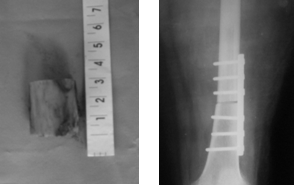

Производится попытка вправления и низведения проксимального конца бедра. При невозможности вправления вывиха наружным доступом в области н/3 бедра производится резекция участка бедренной кости, после чего вправление вывиха и металлоостеосинтез бедренной кости пластиной. С целью правильной установки оперированной конечности в послеоперационном периоде накладывается деротационная гипсовая лонгета по Кепферу. Трехнедельный постельный режим в ходе которого проводится реабилитация аппаратом ППД (рис. 3,4).

Рис. 3 Рис. 4

Нами произведены 4 операции тотального эндопротезирования ТБС при высоких врожденных вывихах бедра с резекций дистального отдела (от 3 до 5 см) бедренной кости.